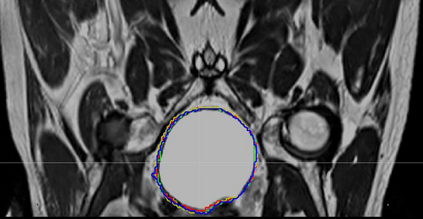

Direct automatic segmentation of objects from 3D medical imaging, such as magnetic resonance (MR) imaging, is challenging as it often involves accurately identifying a number of individual objects with complex geometries within a large volume under investigation. To address these challenges, most deep learning approaches typically enhance their learning capability by substantially increasing the complexity or the number of trainable parameters within their models. Consequently, these models generally require long inference time on standard workstations operating clinical MR systems and are restricted to high-performance computing hardware due to their large memory requirement. Further, to fit 3D dataset through these large models using limited computer memory, trade-off techniques such as patch-wise training are often used which sacrifice the fine-scale geometric information from input images which could be clinically significant for diagnostic purposes. To address these challenges, we present a compact convolutional neural network with a shallow memory footprint to efficiently reduce the number of model parameters required for state-of-art performance. This is critical for practical employment as most clinical environments only have low-end hardware with limited computing power and memory. The proposed network can maintain data integrity by directly processing large full-size 3D input volumes with no patches required and significantly reduces the computational time required for both training and inference. We also propose a novel loss function with extra shape constraint to improve the accuracy for imbalanced classes in 3D MR images.

翻译:3D医学成像的物体,如磁共振成像(MR)成像的直接自动分离,具有挑战性,因为往往需要精确地确定大量调查中大量存在复杂地理不对称的单个物体。为了应对这些挑战,大多数深层学习方法通常会大大提高其模型内可训练参数的复杂性或数量,从而提高其学习能力。因此,这些模型一般需要在运行临床MR系统的标准工作站上花很长的推断时间,并限于高性能的计算机硬件,因为它们的记忆要求很大。此外,要在这些大型模型中安装3D数据集,还要利用有限的计算机记忆,经常使用交换技术,例如补对称培训等,以牺牲从对诊断目的具有临床重要性的投入图像中获得的精细比例的几何地理信息。为了应对这些挑战,我们提出一个具有浅度记忆足迹的银色网络,以有效减少为状态性能所需的模型参数数量。这对于实际就业至关重要,因为大多数临床环境只有低端硬件,计算机功能和记忆有限。拟议的网络可以通过直接处理全尺寸三维化技术来保持数据的完整性,直接处理全尺寸的全尺寸三维的图像,从而大幅改进所需的超度变压的磁度计算。